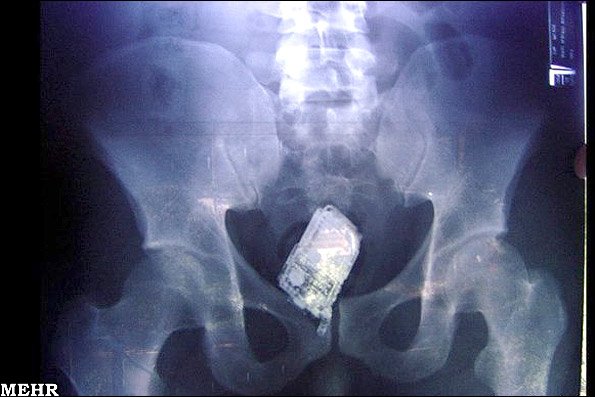

مردانی که تلفن همراه خوردند!

در سپتامبر 2006 تعدادی تلفن همراه در معده چهار زندانی در یک زندان دارای امنیت بالا در السالوادور کشف شد. در این زندان تمام زندانیان مورد عکسبرداری با پرتو ایکس قرار می گیرند.